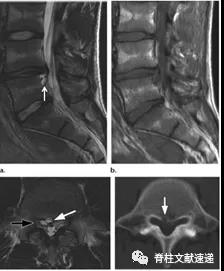

图注:49岁男性,极外侧腰椎间盘突出症。

图注:49岁男性,极外侧腰椎间盘突出症,有黑色素瘤病史。(e) 轴位PET图像显示病灶部位有FDG摄取,怀疑黑色素瘤转移。经过3周的保守治疗,病人的病情有所好转。临床上并没有黑色素瘤诊断。